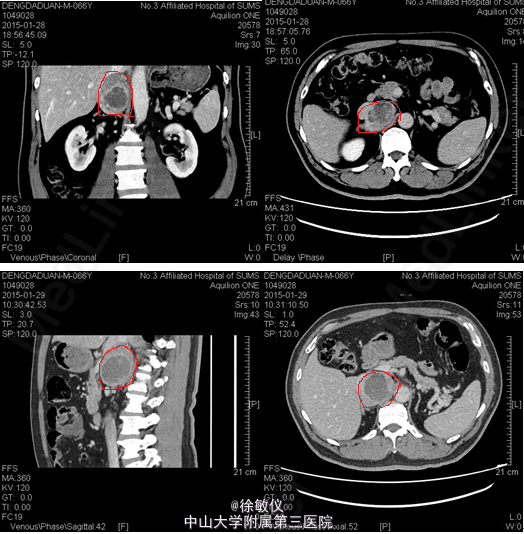

老年男性,发现血压升高40余年,平素规律服用降压药,血压控制差,血压仍可高达200/120mmHg,血压明显升高时有头晕、头痛,偶有恶心、呕吐胃内容物,间中出现双下肢浮肿。患者因血压升高不定期就诊于多家医院,予利尿降压等对症支持治疗,血压控制仍不理想,约170/120mmHg左右。1年余前再次因血压升高检查发现“肾上腺瘤”。现为进一步诊治来我院,双肾+肾上腺螺旋CT平扫+增强示:1、右侧腹膜后肿物,考虑来源于肾上腺内侧支,嗜铬细胞瘤可能性大。血浆皮质醇测定(化学发光法)(8AM):皮质醇617.08nmol/L。血浆皮质醇测定(化学发光法)(4PM):皮质醇272.37nmol/L。血浆皮质醇测定(化学发光法)(0AM):皮质醇104.54nmol/L。高血压三项:醛固酮218.74pg/ml,肾素浓度16.24pg/ml,血管紧张素II232.75pg/ml。